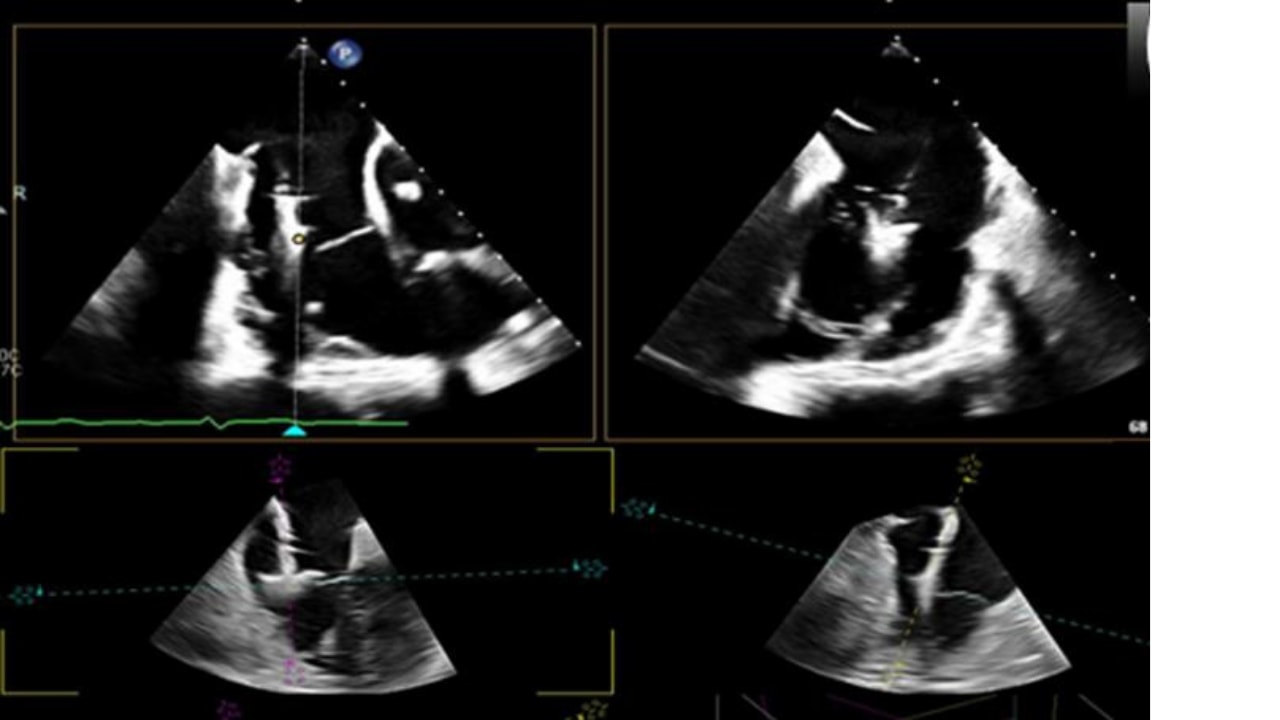

• diagnostica cardiovascolare avanzata non invasiva

e invasiva

per la valutazione

anatomica e funzionale

in ambito interventistiche emodinamico

• diagnostica cardiovascolare avanzata

non invasiva e invasiva

interventistiche emodinamico